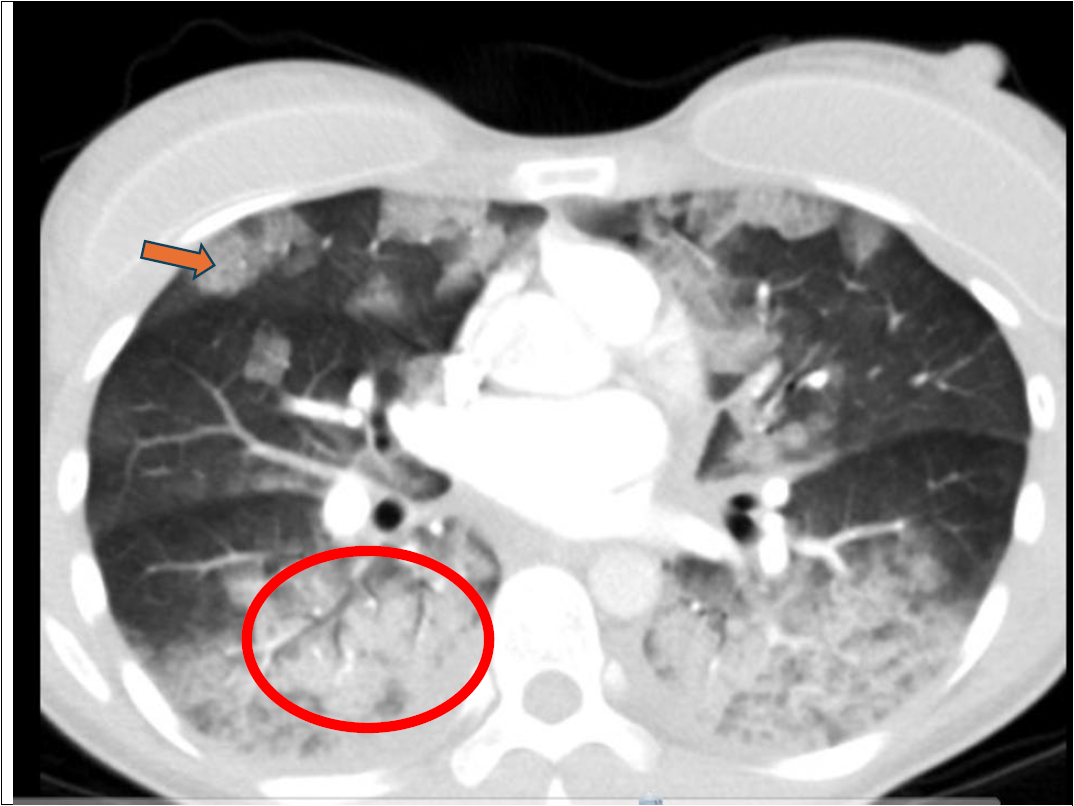

圖三、肺部電腦斷層之冠狀切面(Coronal  view)。

雙側肺部上肺葉有許多毛玻璃樣的變化(ground glass opacity),呈現片狀或是也有擴散狀分佈。此處呈現典型的影像特徵:「crazy paving pattern」(橘紅色箭頭),意指毛玻璃樣的變化加上網狀結構,像“不規則石板/碎石拚鋪的路面”。這些網狀結構,主要是小葉間隔增厚 (interlobular septal thickening) 和小葉內線狀增厚。 常見於肺泡蛋白沉積症 (pulmonary alveolar proteinosis, PAP),感染性肺炎、腫瘤或出血等其他肺部疾病亦會呈現此變化。